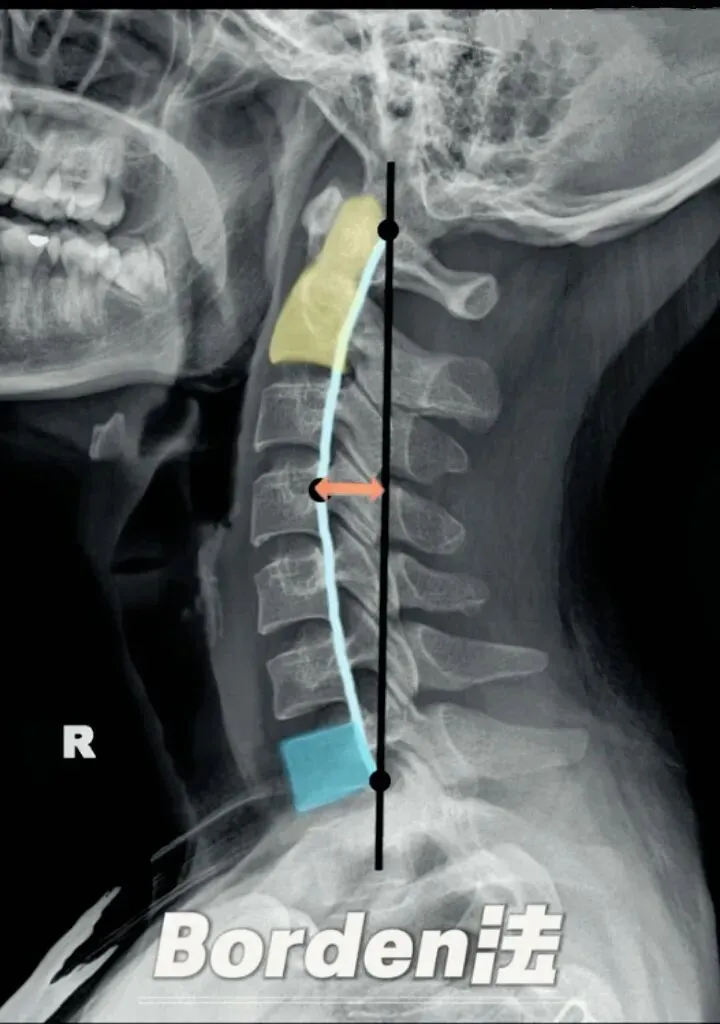

颈椎生理曲度测量的方法多种多样,其中应用最广泛的测量方法是Borden法。从齿状突后上缘开始向下将每个椎体后缘相连成为一条弧线,然后从齿状突后上缘至C7椎体后下缘作一直线测量,两条线间最宽处的垂直横交线的距离即为颈椎生理曲度深度。

正常时,最宽处在C4椎体水平正常为12毫米,正负5毫米,小于7毫米为生理曲度变直,大于17毫米为生理曲度过度前屈,小于零时为生理曲度反曲。